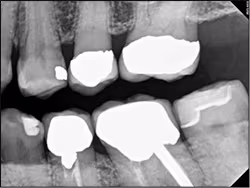

Figure 12. Radiographic image of the patient in Figure 11 after placement of an MO CEREC restoration on tooth #18.

Images courtesy of Dr. Luke Iwata, Loma Linda, CA